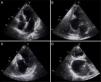

Transthoracic echocardiography revealed a thrombus partially filling a giant pseudoaneurysm/aneurysm of the inferoposterior wall, causing significant deformation of the ventricular geometry (Figure 1; Videos 1–4). Despite the size of the aneurysm, the subvalvular mitral apparatus was intact, with no regurgitation. Given the uncertainty surrounding the differential diagnosis, cardiac magnetic resonance imaging was performed, which confirmed a giant ventricular aneurysm (long axis 6.7 cm) containing a thrombus (Figure 2; Videos 5 and 6), and anticoagulant therapy was begun. Myocardial perfusion scintigraphy excluded ischemia and confirmed necrosis of the inferoposterior territory. Preoperative cardiac catheterization showed chronic occlusion of the proximal right coronary artery but no significant left coronary disease, while ventriculography documented a large ventricular aneurysm (Figure 3; Video 7). The patient underwent surgical repair of the aneurysm of the left ventricular inferior wall (Figure 4) by partial aneurysmectomy under extracorporeal circulation, with removal of a large wall thrombus and closure of the aneurysm neck with a 2 cm × 3 cm Dacron® patch (Figure 4). The left ventricle was closed using continuous sutures. The postoperative period was uneventful and the patient was discharged home on the fifth postoperative day.

Two-dimensional transthoracic echocardiography: (A) apical 4-chamber view showing no alterations; (B) apical 2-chamber view revealing a giant ventricular inferior wall aneurysm containing a thrombus; (C) modified apical 2-chamber view showing intact subvalvular mitral apparatus; (D) modified apical 3-chamber view showing a large ventricular posterior wall aneurysm containing a thrombus.